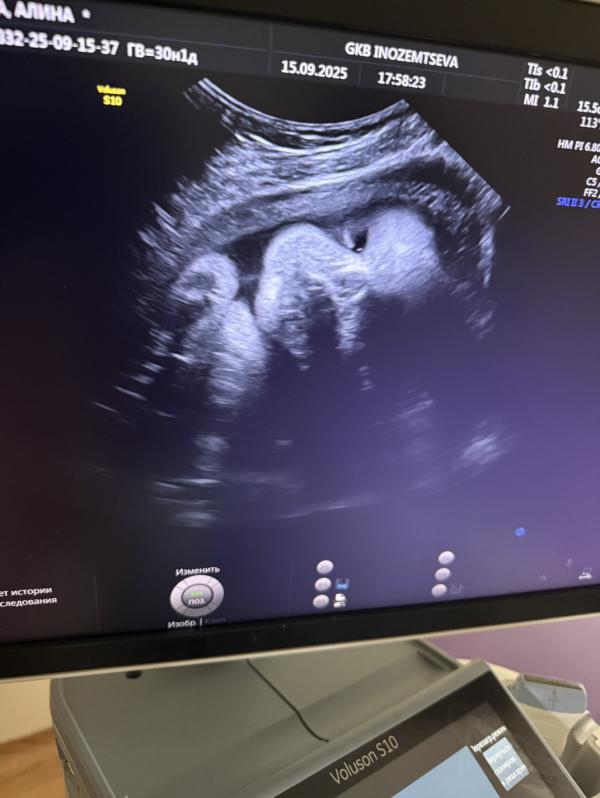

Не везет в эту беременность на нормальные фотки с УЗИ😅, но главное, что все хорошо, ттт 1700 уже, опережает чуть срок с 1 скрининга. 💕💕💕Чую дочь будет крупнее сына